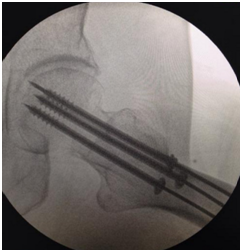

将克氏针紧贴于骨表面插入,可以为后续的钻孔、置入螺钉提供导向作用,提高成功率,常用于骨盆、股骨颈、股骨髁等位置。